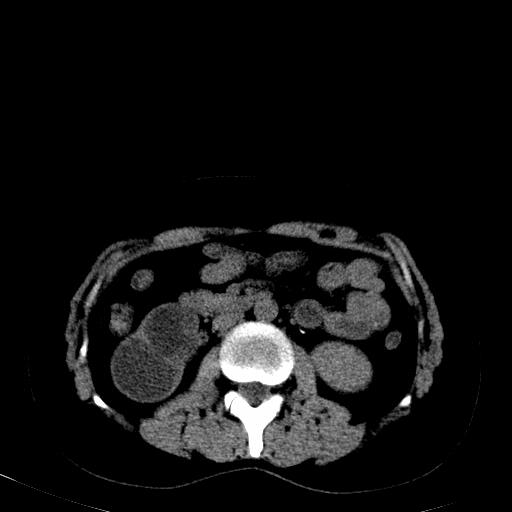

患者体检发现右肾体积增大,怀疑右肾积水

右肾多发囊肿,左肾、左输尿管结石

右肾重度积水,以肾盏积水明显,有分隔,上段输尿管轻度扩张,管壁增厚,考虑肾结核可能,请结合尿检查,胸部拍片排除肺结核。

右侧肾积水、左侧肾结石

右侧肾积水、左侧肾结石  ,要排除右肾结核可能。

右肾重度积水,建议ct向下扫描或逆行造影,左肾及左输尿管结石 .

右侧肾积水、左侧肾结石 ,原因待查

患者尿常规正常,b超未发现明显结石,自身也无明显感觉异常。

请问多囊肾与肾积水怎么鉴别